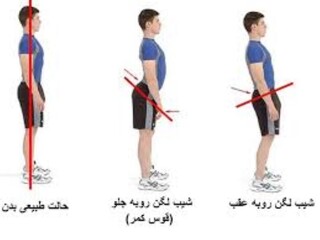

/فیلم آموزشی/

ناهنجاری کمر گود یا لوردوزیس

رحمت اله خان محمدی/مسئول حرکات اصلاحی هیات پزشکی ورزشی استان خوزستان